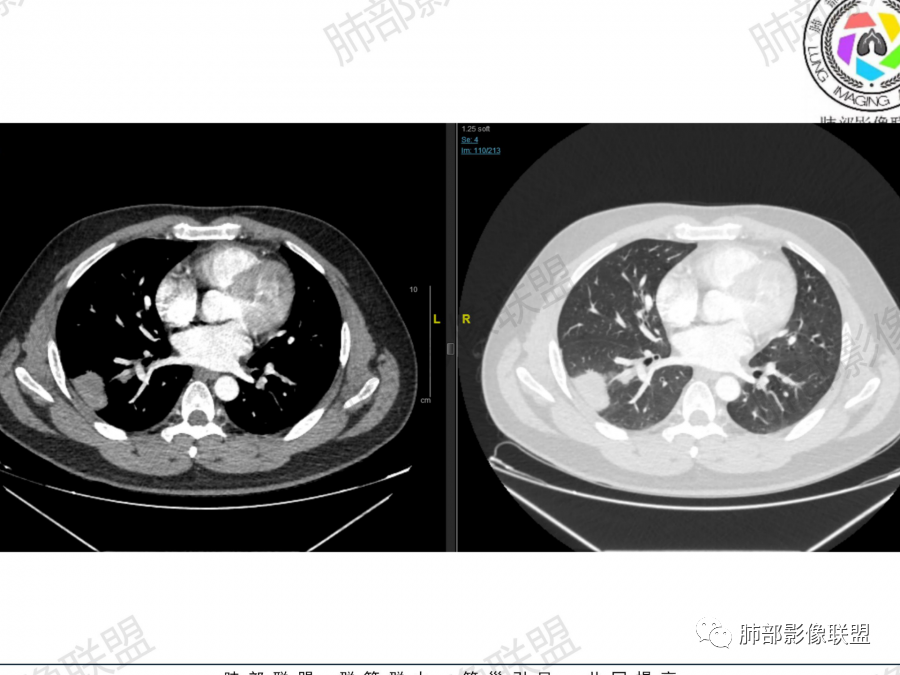

1、青年男性、咳嗽气喘一月,加重两天入院。实验室检查:有铁蛋白增高,血脂、肝功异常、有免疫异常。

2、右肺多发结节影,大者位于右肺上叶尖段,内可见空洞,空洞内壁欠规整,内可见分隔,余结节位于胸膜下、结节大小不等、形态相近,强化均匀,内部可见血管穿行,血管及支气管走行自然。结合临床及影像,符合隐球病。

多发结节或实变型:分布多为下叶单叶胸膜下、少数两肺多发、多叶段分布。弥漫型:本例为单侧肺、多叶结节型。

2、隐球菌感染有时相性,初期的隐球菌感染周围有晕征,晕从多变少,或包裹,或吸收,结节实性区可迅速变大,后期(慢性期)的隐球菌周围无明显晕征,边界较清楚。本例病变发病一月, 为后期,晕征不明显。